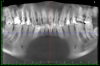

Born486 Опубликовано 23 мая, 2012 Поделиться Опубликовано 23 мая, 2012 Добрый вечер. Хотел бы получить совет специалистов. Интерисуют зубы под №14, 15, 16. Зубы не болят, но довольно сильно разрушены (были большие пломбы со штифтами, но со временем сломались стенки зубов (№15,16), лечение проводилось от 2-5 лет назад.Рекомендации от врачей:15 - зуб первый кандидат на удаление.16 - удаление или перепломбировка каналов (при помощи ультразвука) , резекция верхушки корня, штифтовкладка.14 - пока под вопросом.Ну вот как-то так! Ссылка на комментарий

ger_berra Опубликовано 23 мая, 2012 Поделиться Опубликовано 23 мая, 2012 16 -полностью перебрать.Сохранить можно.15 - 99.9% удалять14 - перебрать. Ссылка на комментарий

kriokov Опубликовано 23 мая, 2012 Поделиться Опубликовано 23 мая, 2012 по КТ - 16 и 15 удалил бы. Ссылка на комментарий